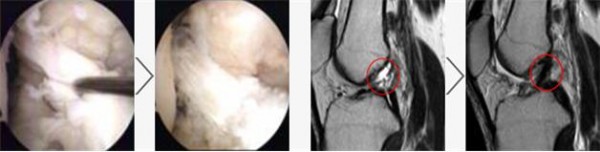

진료와 상담을 통해 어 느정도 진단이 가능하며, 확진은 MRI 검사와 관절내시경을 통해 가능합니다.

X-Ray 촬영으로는 인대손상을 정확히 확인 할 수 없음

MRI나 관절내시경으로 관절낭, 반월상연골 등도 손상 되었는지 확인해야함

십자인대 수술사진 및 mri 영상